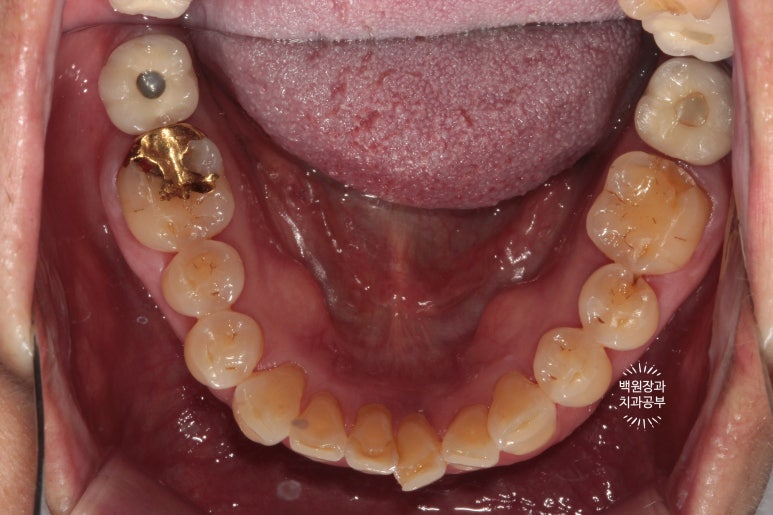

아래 어금니 떼운게 떨어졌어요. 썩은 것 같아요.

: 큰어금니 골드인레이 탈락하고 2차 충치 발견!

사진상에서 금니가 보이시나요?

떨어져서 가지고 오신 것을 제가 끼워놓은 상태입니다.

왜냐! 2차충치가 있음을 더욱 명확히 보여드리기 위해서입니다.